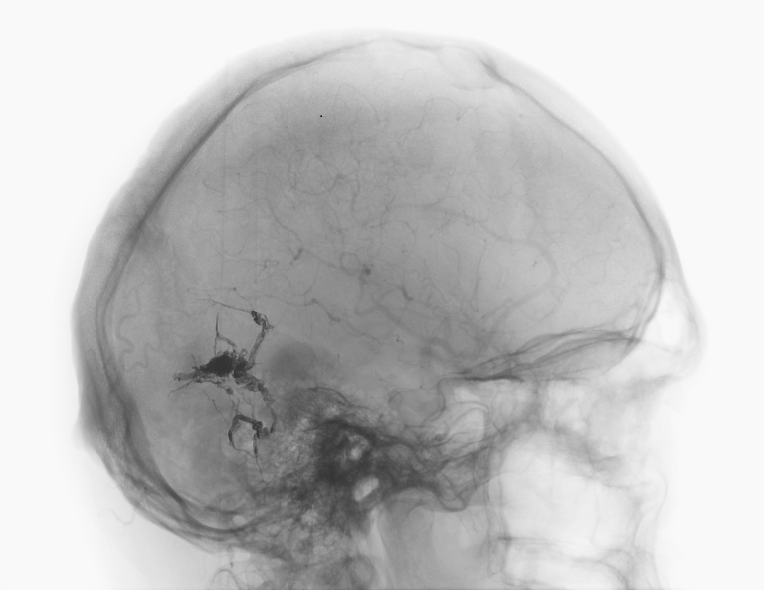

AV Fistula

Arterio-venous fistulas (AV fistulas) can occur in the brain and spinal cord, leading to many different symptoms. In addition to harmless symptoms, such as so-called pulse-synchronous ringing in the ears, bleeding with neurological deficits can occur or spinal cord symptoms with gait disorders and even paraplegia with incontinence.

AV fistulas are often challenging to diagnose and can be very complex. It is essential to differentiate between "dangerous" and "harmless" AV fistulas and determine the appropriate treatment.